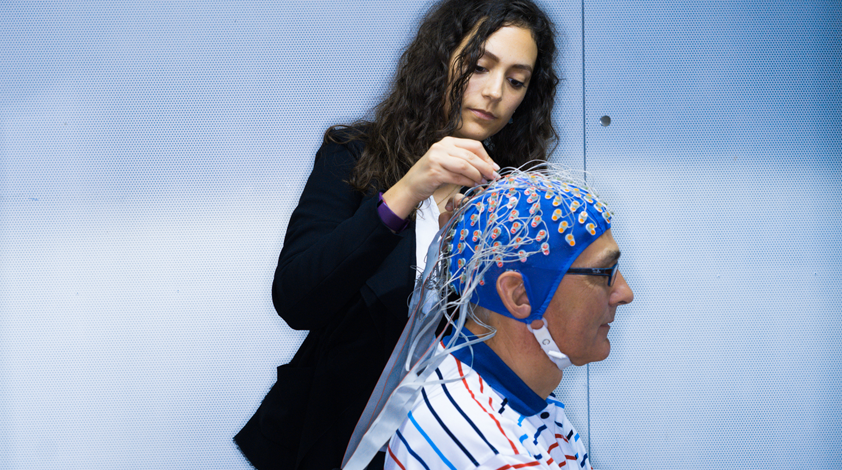

The study*, which lasted two-and-a-half years, saw Giroud investigating how well and how quickly the brain is able to learn in old age. Her research is globally unique in that it represents the first successful attempt in a long-term study to scientifically measure the efforts the brain makes to react to language. The 15 younger and 45 more senior test subjects selected for the study took part in hearing tests at regular intervals over a period of several weeks. The group of older test subjects included both hearing aid wearers and people unaffected by hearing loss.

During the hearing test, all the test subjects were required to distinguish between various syllable pairs (such as “asha” and “afa”, for example), sometimes under difficult conditions. “As the syllables differ by only one sound, “sh” or “f”, in a high frequency range, older people affected by hearing loss really struggle to detect this contrast,” explains Giroud. 256 electrodes attached to the scalp were used to detect and conduct the brainwaves, and these were digitized using an EEG (electroencephalograph). “We were thus able to see the extent of the neuronal effort, in other words, how many brain cells each test subject had to activate to register the difference between the syllables,” explains Martin Meyer, Professor of Neuroplasticity at the University of Zurich; as Nathalie Giroud’s doctoral supervisor, he was responsible for overseeing her project.